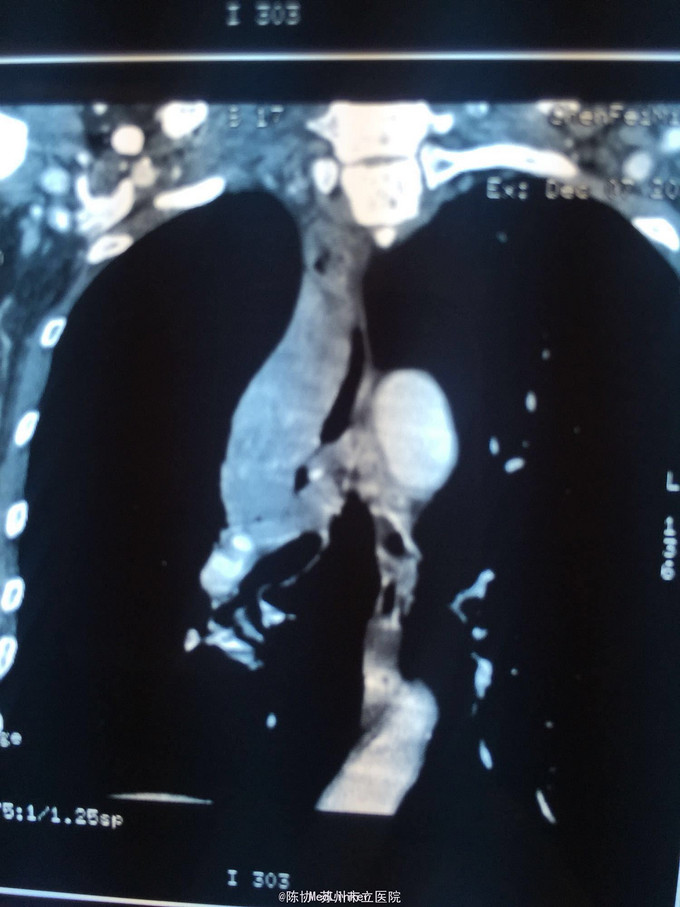

主诉:体检发现右上肺不张半月 77岁男,半月前体检发现右上肺不张,无不适。无消瘦,无咳血,无干咳。去年4月右上肺炎,抗生素治愈,当时CT未见肺肿块。入院支气管镜发现右上支气管开口组织增厚闭塞,开口近侧有隆起约3x3平方毫米,取活检5块病理示中度非典型增生。CT提示在右侧主支气管外侧有30x30平方毫米块影,压迫右上支气管开口处。三大常规和生化检查正常,肿瘤指标正常,TAP正常。

右侧中央型肺癌 重做支气管镜,精于定位找到病症组织,获得病理诊断来指导治疗。 胸外科医生不建议手术,理由是肿瘤位置靠近主支气管和气管,袖状切除不一定看干净。 请问正确的诊断,和比较合理的治疗方法是什么?求助大家思考评论